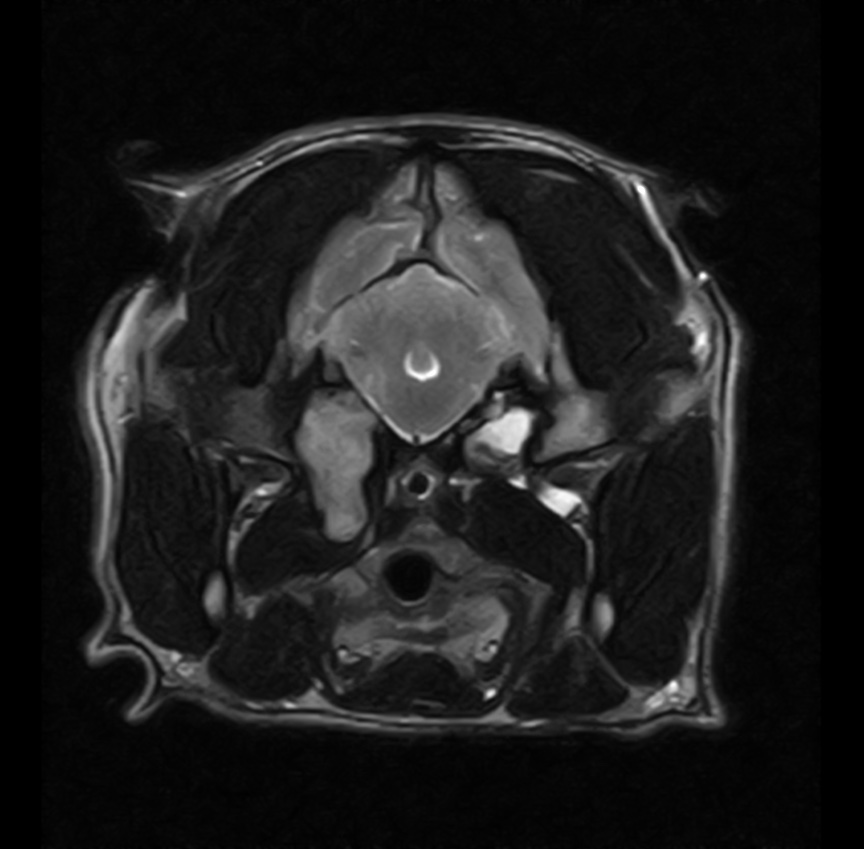

フレンチ・ブルドッグの真珠腫性中耳炎

2025/01/29